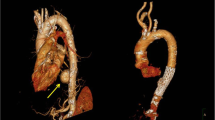

Depending on the forces in play, the aorta injury site can be the root, ascending aorta, arch, isthmus, descending aorta or even abdominal aorta (less common). Multiple studies in deceased and surviving patients show the aortic isthmus is the most common location of injury. However, since studies are not inclusive of all blunt trauma-related fatalities, there may be a shift in numbers with more injuries potentially occurring at the aortic root. A considerable number of patients has aortic injury at multiple sites, in the autopsy series by Teixeira et al. amounting up to 18 % (Teixeira et al. 2011) (Fig. 2). In that study, 2 % of injuries were located at the aortic root, 3 % at the ascending aorta and 11 % at the arch. Mention is warranted for the other upper thoracic major vessels, especially the aortic arch branches, which can be injured in isolation. In a small sample study by Chen et al., 38 % of injuries involved the proximal aortic arch branching vessels (Chen et al. 2001). Even though the percentage likely is lower, injury to these vessels is important to diagnose and treat if necessary.

Example of multilevel blunt traumatic aortic injury on sagittal CTA (a) with corresponding axial CTA slides (b, c). The proximal intimal injury (solid white arrow) was most likely caused by a stretch mechanism; the distal intimal flap (open white arrow) may have been caused by stretch and/or direct impact from the nearby vertebral fracture (arrow head)